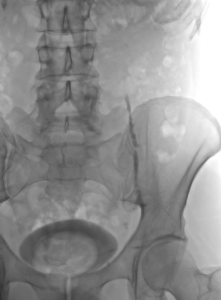

L’embolisation de la varicocèle est réalisée en salle de radiologie interventionnelle. Le patient est allongé sur la table d’examen, et une anesthésie locale est réalisée soit au bras soit à la cuisse pour minimiser l’inconfort. Un petit cathéter est inséré dans une veine, à l’aine ou au bras droits, sous guidage radiologique. Le cathéter est placé à l’aide des rayons X dans la veine testiculaire (en général à gauche si la douleur siège à gauche) et une occlusion est réalisée à l’aide de colle (Glubran 2 par exemple) ou de coïls. La veine dilatée est maintenant occluse et le sang aura un retour non pathologique avec une redirection du flux sanguin. La procédure prend généralement moins d’une heure.